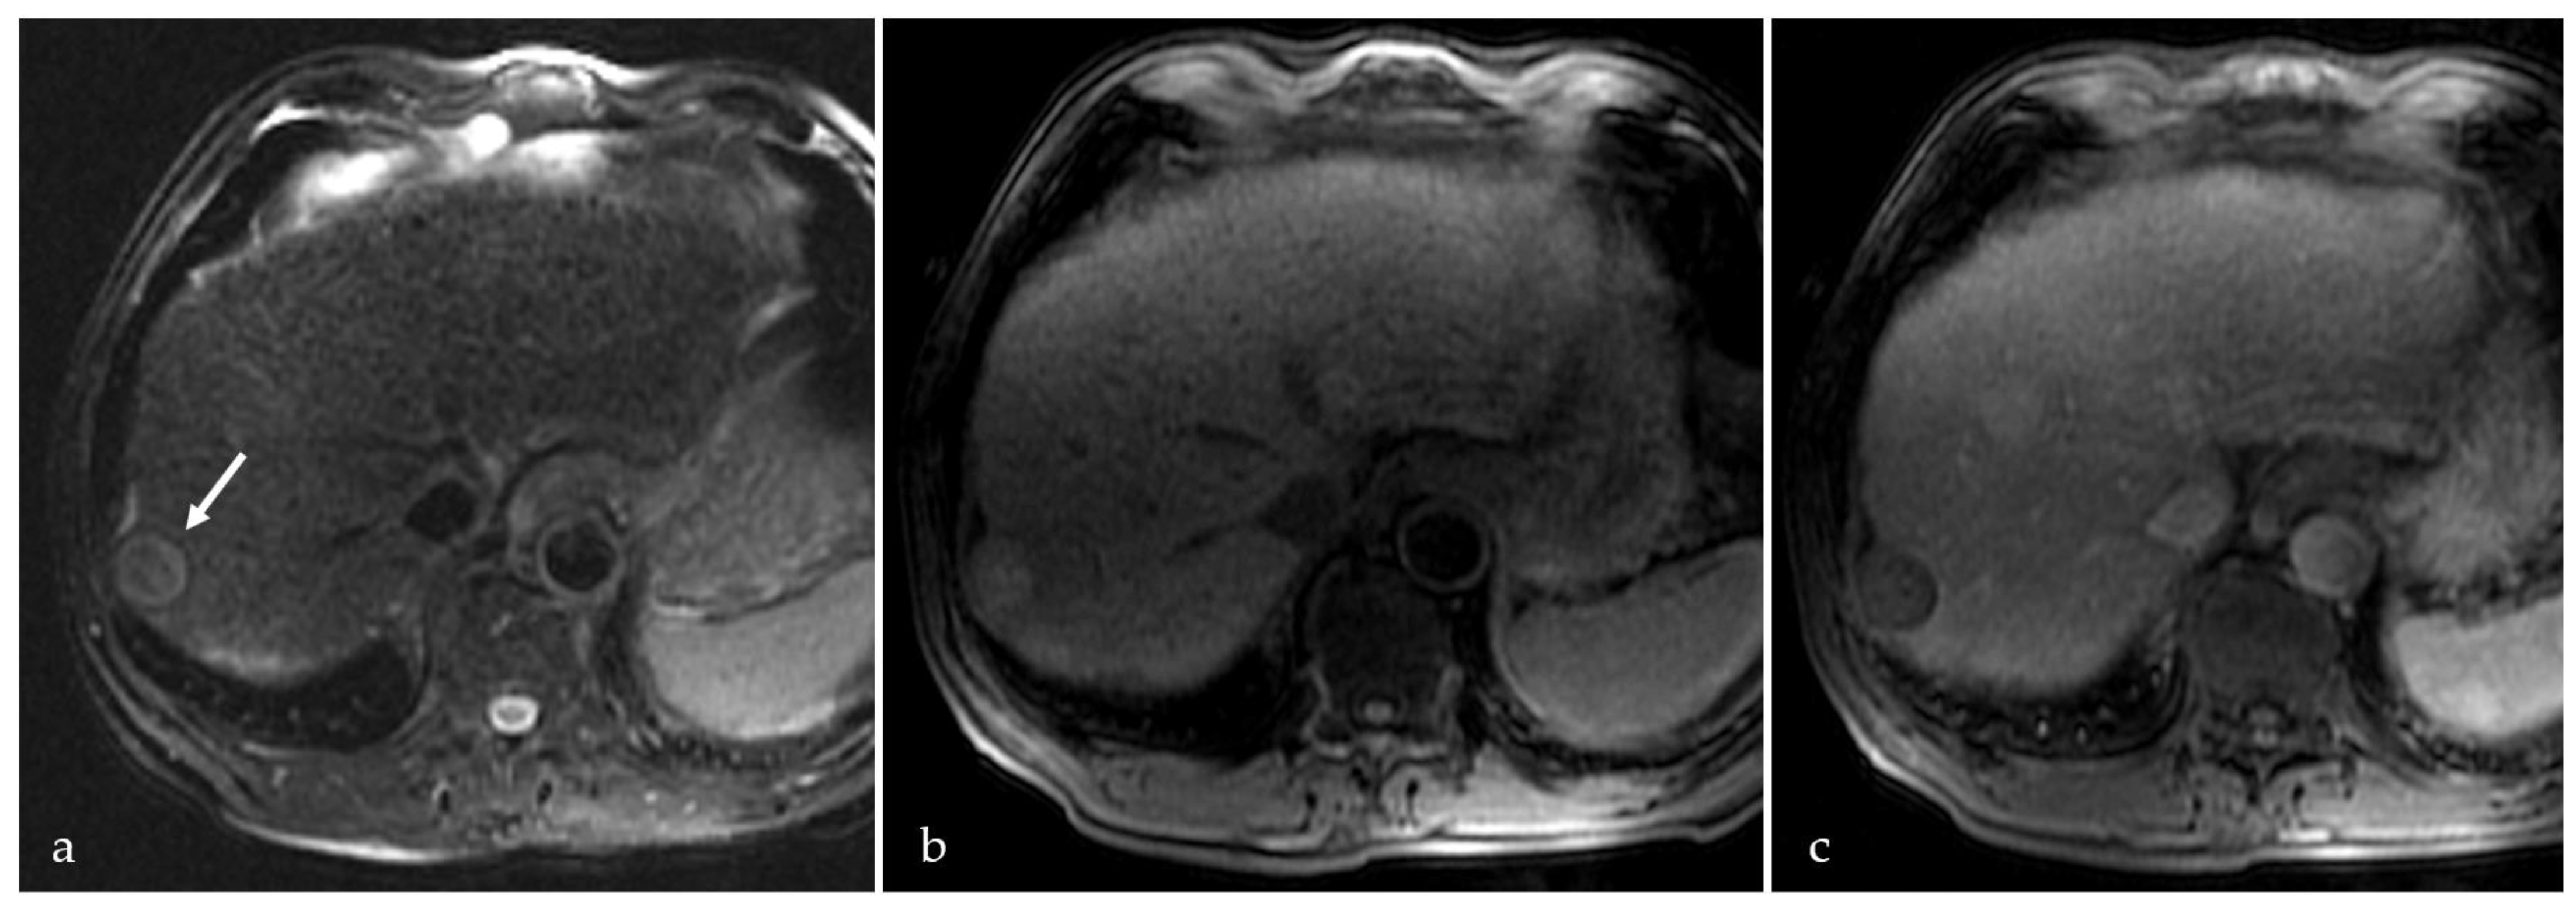

3.2. Expected Post-Treatment Imaging Features in the Absence of Viable Tumor Tissue

3.3. Transient Hyperemia